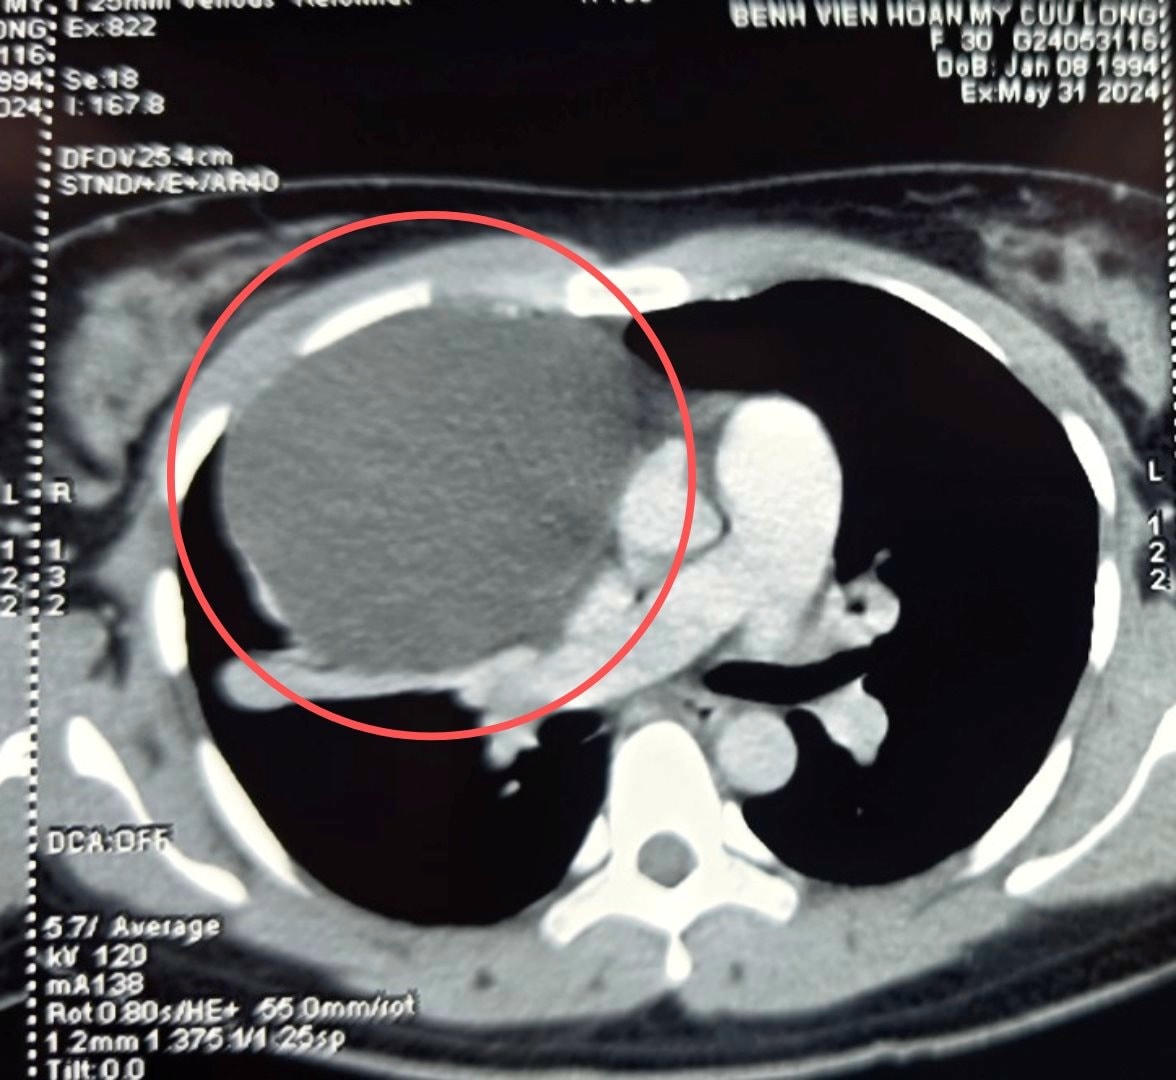

Các bác sĩ ở Cần Thơ vừa phẩu thuật cắt bỏ toàn bộ khối u nang trung thất to 15 cm (nặng khoảng 200 gram) đang chèn ép tim, phổi người phụ nữ 30 tuổi.

Gần đây, chị M ho khan tức ngực nhiều hơn, đặc biệt khi nằm. Chị đến Bệnh viện Hoàn Mỹ Cửu Long kiểm tra lại thì được chẩn đoán là u trung thất có kích thước lớn chèn ép tim và phổi phải, khối u vẫn đang tiếp tục phát triển.

Sau gần 1 giờ phẫu thuật, ekip bác sĩ đã cắt bỏ toàn bộ khối u nang trung thất to 15 cm (nặng khoảng 200 gram)mang ra ngoài chỉ qua 3 vết mổ nhỏ từ 5 - 10mm. Sau 2 ngày phẫu thuật, người bệnh đã hồi phục tốt, hết ho khan, tự ăn uống, sinh hoạt được, chỉ số sinh hiệu bình thường và xuất viện sau 3 ngày điều trị.